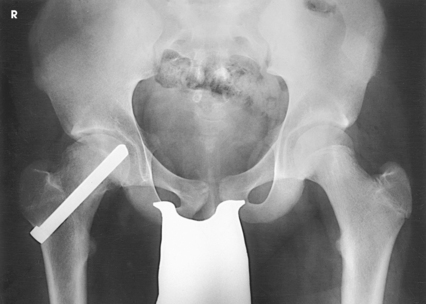

Structures shown: The resulting image shows the head, neck, trochanters, and proximal one third of the body of the femur (Fig. 7-31). In the initial examination of a hip lesion, whether traumatic or pathologic in origin, the AP projection is often obtained using an IR large enough to include the entire pelvic girdle and upper femora. Progress studies may be restricted to the affected side.

Structures shown: The resulting image shows the acetabulum, head, neck, and trochanters of the femur (Fig. 7-37).

CLEMENTS-NAKAYAMA MODIFICATION

When the patient has bilateral hip fractures, bilateral hip arthroplasty (plastic surgery of the hip joints), or limitation of movement of the unaffected leg, the Danelius-Miller method cannot be used. Clements and Nakayama1 described a modification using a 15-degree posterior angulation of the central ray (Fig. 7-38).